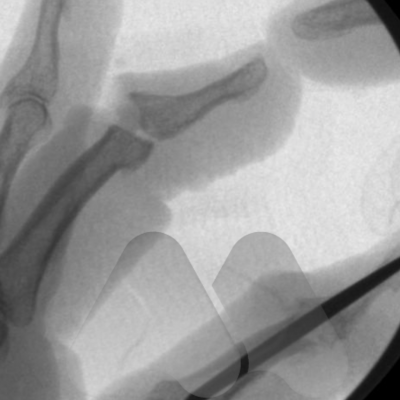

Arthrodesis

This is the technique of fusing the joint in a position of best function that is appropriate to each individual patient. This is a very durable and reliable way of relieving pain and correcting severe deformity although it does prevent any movement of the affected joint from the fused position. It has been a technique employed since the early 1900’s with good long term results. It is particularly useful in younger patients with a requirement for heavy manual activity and commonly used to treat arthritis in the smaller joints of the fingers such as the DIP joints but can be performed in almost any joint. Risks of surgery include a failure to fuse the joint causing ongoing pain, risk of implant breakage or irritation to surrounding tissues, injury to surrounding structures including skin, nerves, blood vessels and cells that produce the nail and can also be complicated by infection.